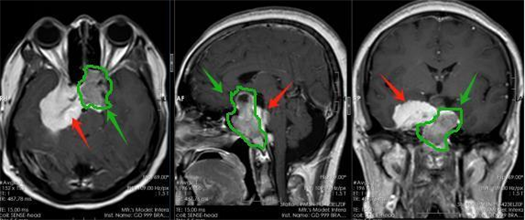

该院副院长鲁明接诊后,发现患者鞍区占位约3cm,压迫视神经引起视力下降,考虑为垂体瘤;蝶骨嵴、海绵窦、斜坡占位约5.2cm,引起颅高压症状,考虑为脑膜瘤。尽管两个肿瘤相邻,但体积均较大且位置特殊,难以一次性切除。

▲术前影像:绿色箭头考虑为垂体瘤,红色箭头考虑为脑膜瘤